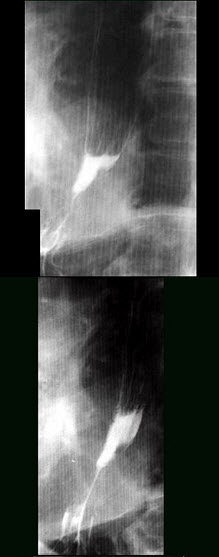

12、单项选择题

女,65岁,进行性吞咽困难半年,消瘦,钡餐检查如图,最可能的诊断是()

A.贲门失弛缓症

B.食管静脉曲张

C.食管鳞状(上皮)细胞癌

D.贲门癌

E.返流性食管炎